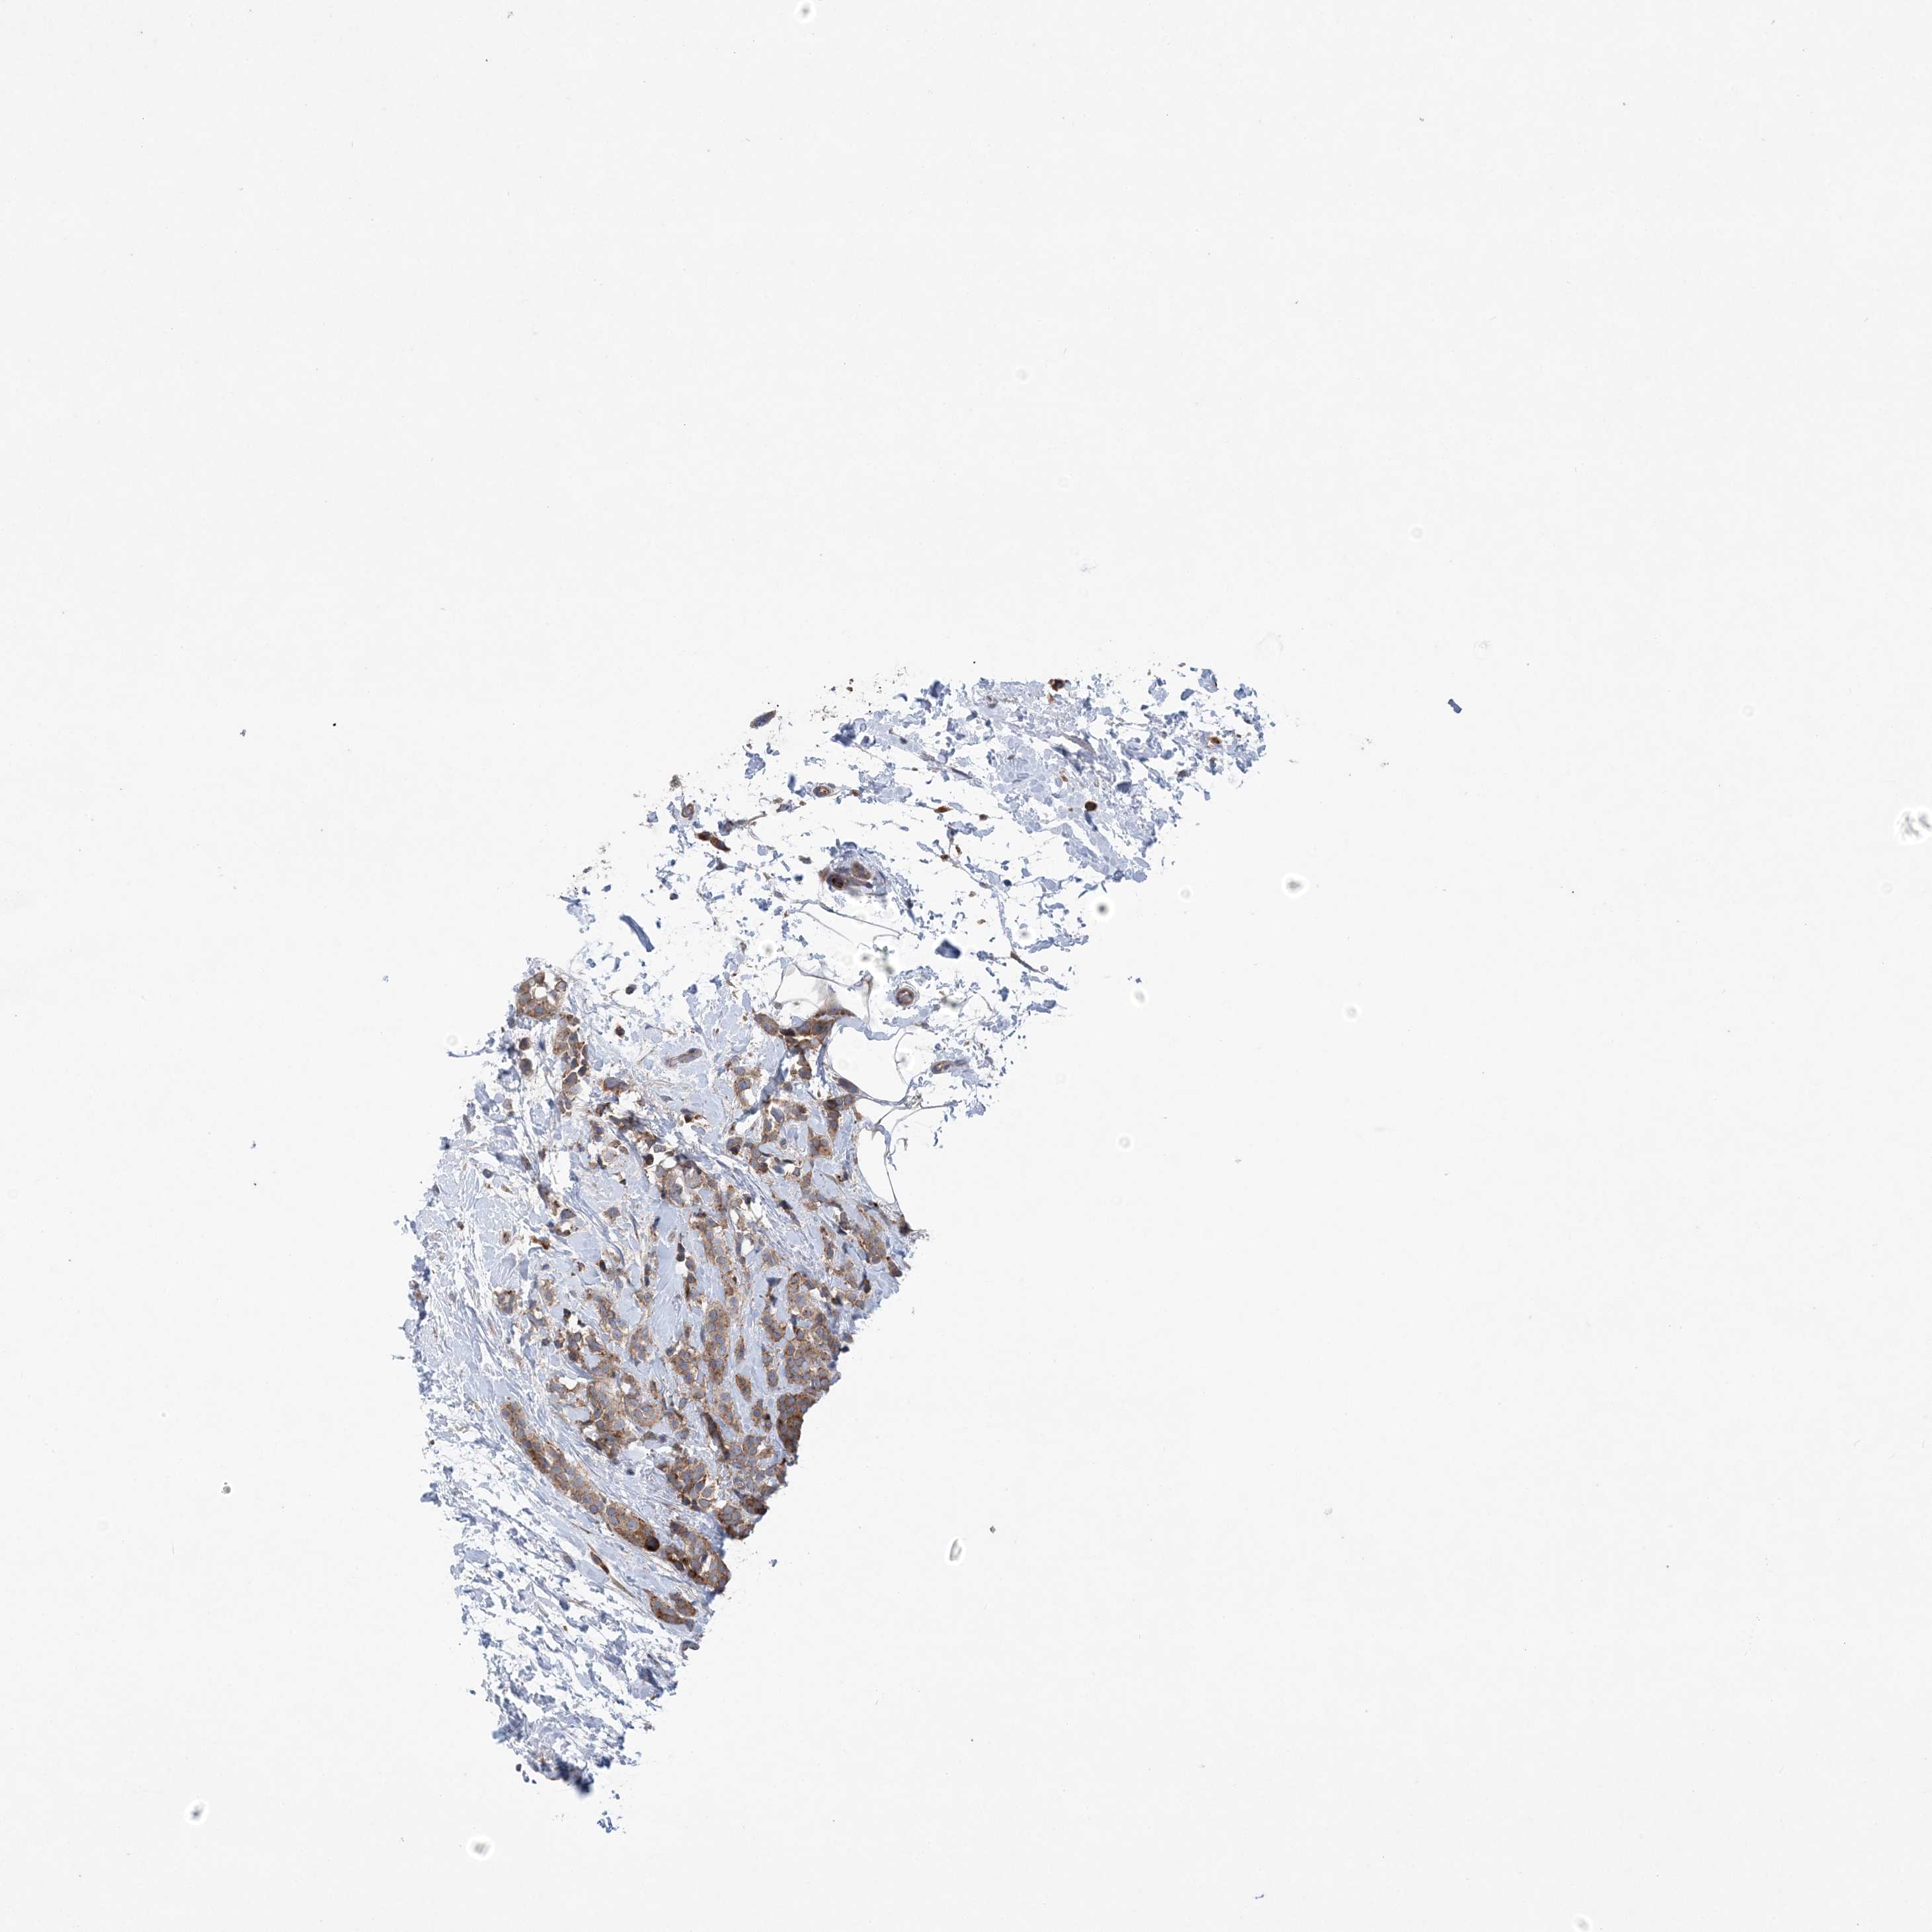

BRCA TCGA BRCA VALIDATION PROTEIN EXPRESSION